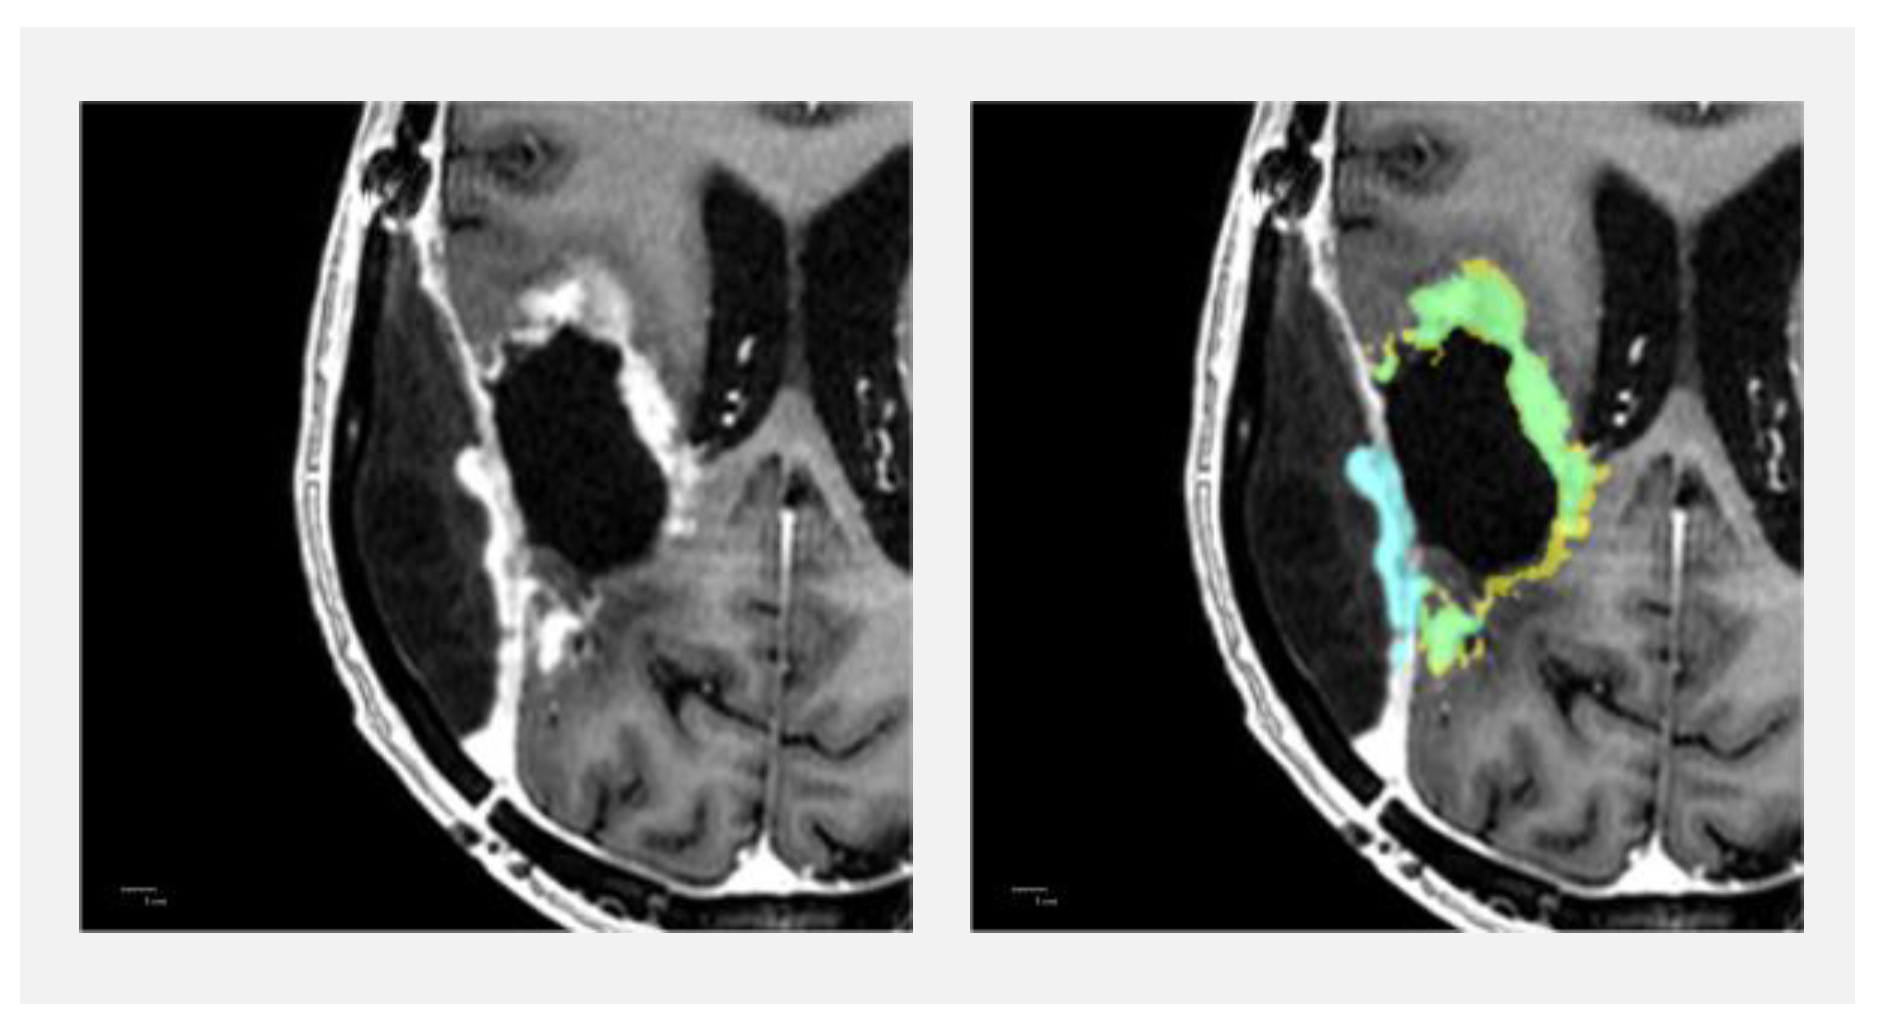

3.2. Contrast-Enhancing Tumours

3.4.2. Non-Enhancing T2 Hyperintense Abnormality Lesions